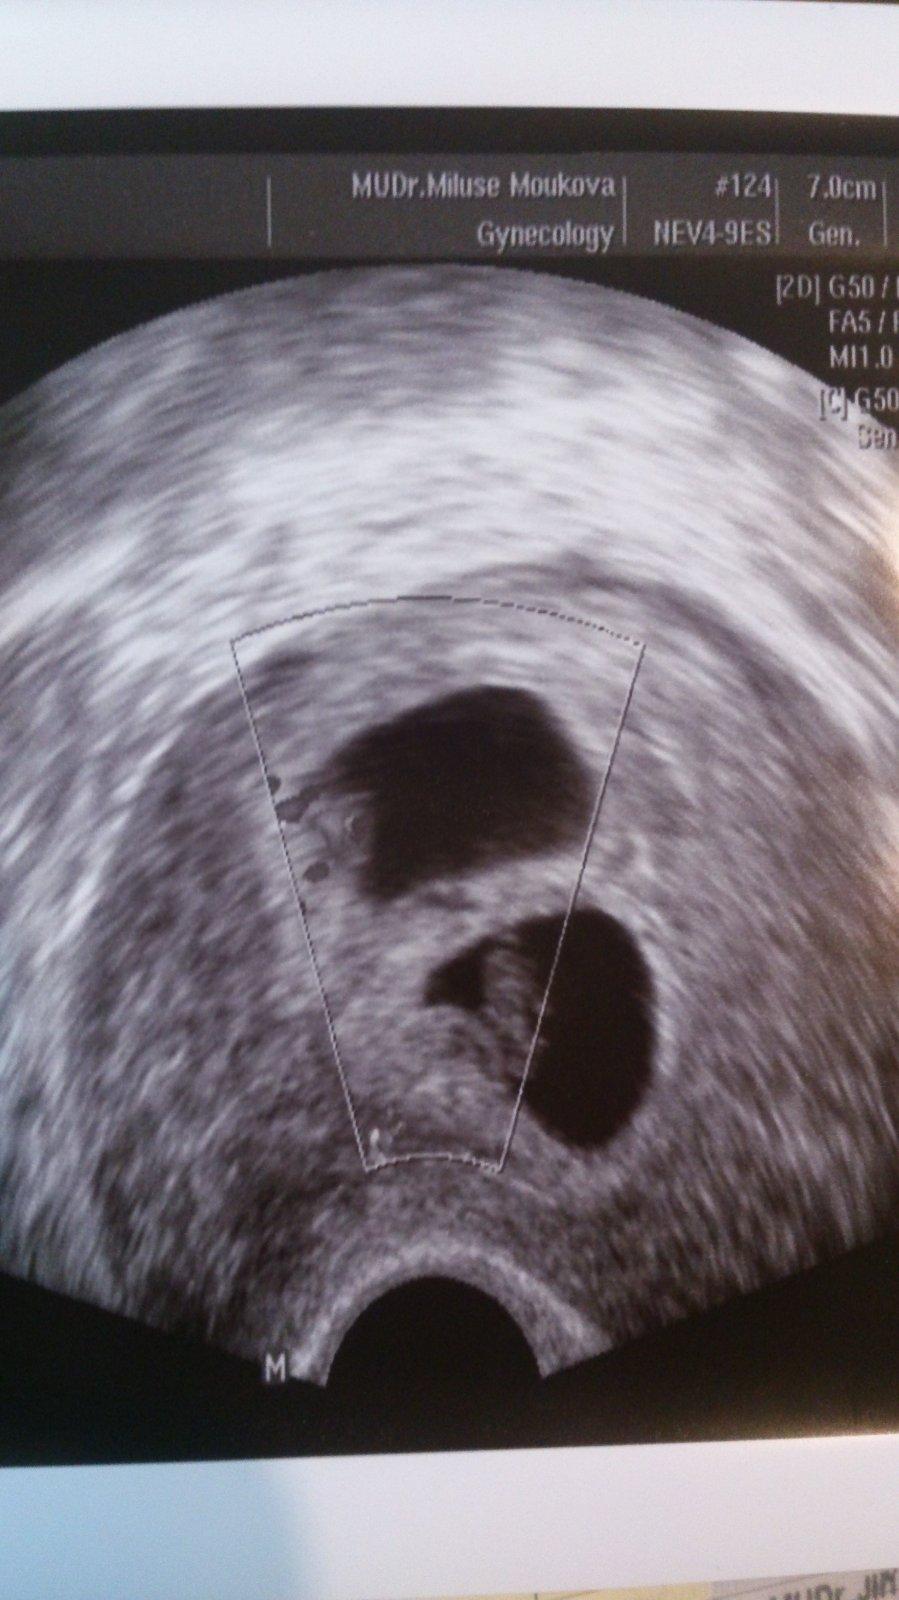

@kure18 holky držím vám moc moc palce, ať vydržíte co to půjde. Já jsem ještě o 3 týdny pozadu oproti vám a k 30. týdnu se hodně upínám, je to pro mě takový zlom, kdy se aspoň trochu hodit do klidu, protože mám velký strach z předčasného porodu. Čekáme jednovaječná dvojčata s jednou placentou, takže každý den za námi je pro nás malé vítězství. Často mám ale problémy s tím nebo oním a plaším, jestli je to normální, je to moje 1. těhotenství. Ať to bude kdykoliv, tak rodit budu v FN Ostrava, už tam docházím stejně do rizikovky.

Mimochodem vím, že dotaz nebyl určený mě, ale mě už spoustu lidí nebo lékařů řeklo nebo naznačilo, že budu rodit brzy a že nevydržíme do 36, 37tt, kdy se nejpozději ukončuje těhotenství mono-bi.